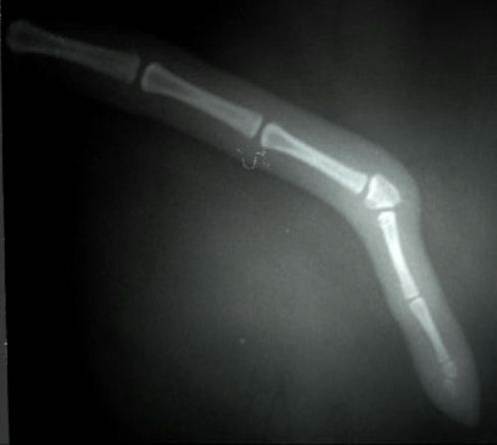

Сломанный хвост у собаки

Сломанный хвост у собаки 110 фотографий